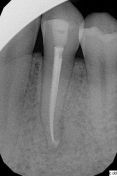

La paziente si presenta per un problema al 34. Presenza di dolore alla masticazione, sensazione di dente allungato, il test pulpare è positivo, dolore alla percussione e alla palpazione, assenza di mobilità dentale. L' rx endorale conferma la presenza di una lesione apicale acuta ipotizzata all'esame clnico. La terapia è endodontica.